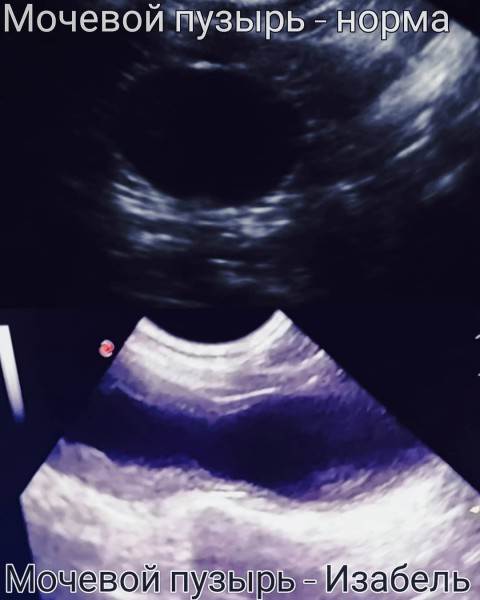

Мочевой пузырь кошки Изабель на УЗИ

На снимках, используемых в этой статье, кошка Изабель — являющаяся показательным примером того, что случится с органами мочевыделительной системы «спинальника», если животному не опорожнять мануально мочевой пузырь. Изабель утратила функцию произвольного мочеиспускания в возрасте котёнка, после чего целый год жила в приюте для бездомных животных, где не знали о необходимости мануально опорожнять мочевой пузырь кошке, которая не может осуществить диурез самостоятельно. За самостоятельное мочеиспускание воспринималось протекание по каплям на фоне переполнения.

Постоянное переполнение и перерастяжение мочевого пузыря превратили когда-то упругий «шарик» (мочевой пузырь) в растянутую атоничную «тряпочку». Качественно мануально опорожнять этот мочевой пузырь сейчас — очень тяжело даже опытным ветеринарным врачам.

Но самое главное — воспалительный процесс, возникший в мочевыделительной системе на фоне «неотжимания» привёл к заболеванию, а потом и к «гибели» одной из почек. На снимках можно увидеть разницу между функционирующей почкой и нефункционирующей.

Это очень важно, обратите на это внимание — Изабель осталась с одной функционирующей почкой, потому что ее мочевой пузырь не опорожняли мануально, а не наоборот.

Миф, который мы разобрали, заключается в том, что мануальное опорожнение мочевого пузыря приводит к «смерти» почек, а в действительности же эта кошка продолжает жить (и живёт качественно и комфортно уже 1,5 года после того, как ее доставили в ветеринарную клинику «сгнившей») только благодаря тому, что ее наконец-то начали отжимать!